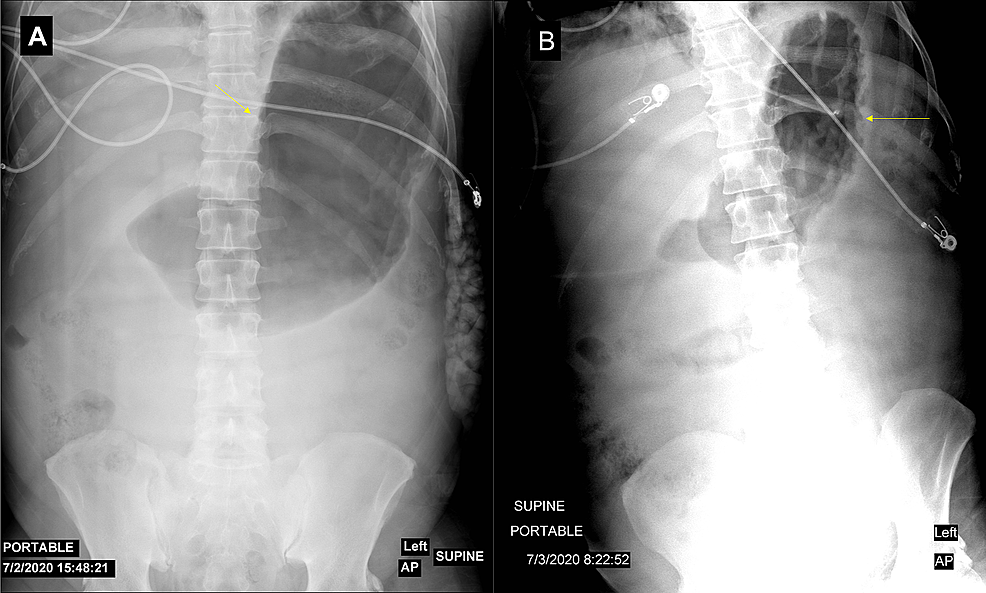

An ultrasound of the gallbladder was done upon admission, which showed no evidence of biliary stones. The patient was kept nil per os (NPO) and was started on 250 mL/h of lactated Ringer’s solution. The pain was controlled with intravenous hydromorphone, and the patient was transferred to the ICU for close monitoring. After six hours, the abdominal pain worsened, and the patient developed abdominal distension and increased bladder pressure (34 mmHg). A kidney, ureter, and bladder (KUB) X-ray revealed significant gastric distention (Figure 2A). Given the suspicion of abdominal compartment syndrome (ACS), the patient was placed in a supine position and received muscle relaxants. A nasogastric tube (NGT) was inserted and the surgical team was consulted. The patient was managed with these conservative measures, and a follow-up KUB (Figure 2B), bladder pressure, and abdominal examination showed significant abdominal decompression.

As ileus and gastroparesis are often present in acute pancreatitis, reducing the intraluminal volume of the gastrointestinal tract is a logical first step. In the case of gastric dilatation, nasogastric decompression can easily be done and may have a significant impact on IAP [20]. Our case, with severe IAH, showed an excellent response to the insertion of NGT and the use of muscle relaxants.